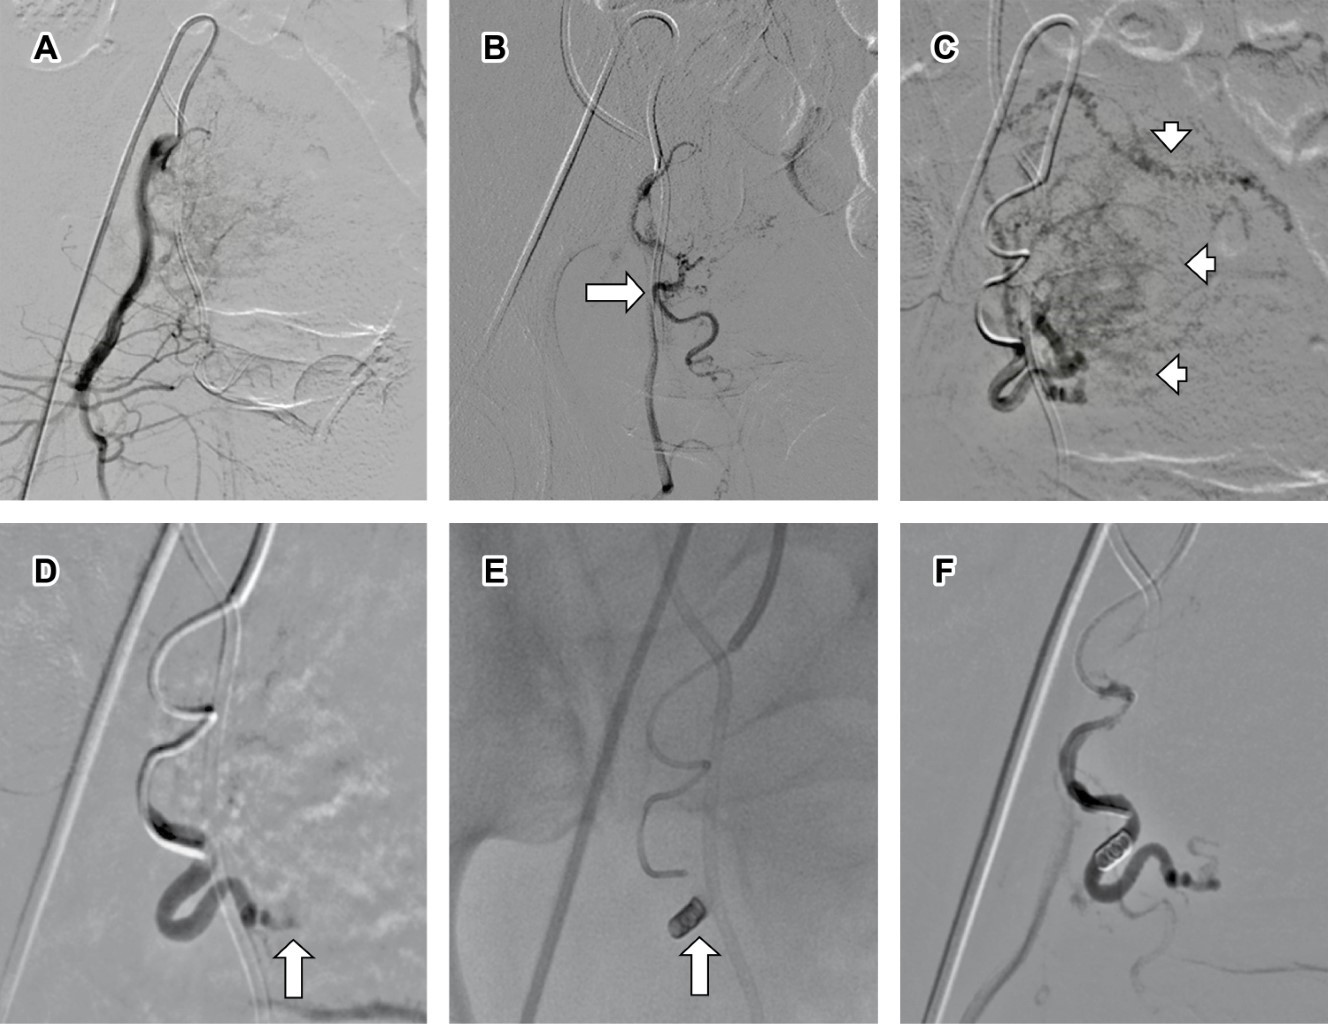

En el lado derecho, el procedimiento se repite con un catéter Simmons de 5 Fr, utilizando emboesferas de 300-500 y 500-700 micras debido al aumento de vascularización en el fondo uterino. Se coloca un coil de 3 mm × 8 cm en el tronco de la arteria uterina y se confirma la embolización completa, así como la preservación de la vascularidad pélvica (Figura 3).

Figura 3